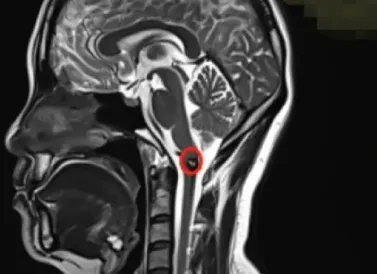

腦干-延髓海綿狀血管瘤影像